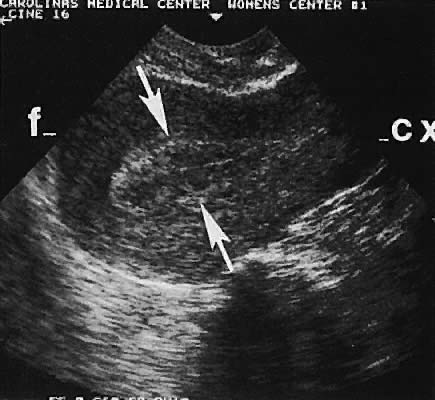

Transvaginal ultrasonography offers the opportunity to visualize the endometrium (Figs. 27 and 28). To select patients at an increased risk of endometrial disease, several authors have evaluated the reliability of inferring endometrial histologic changes from measuring the width of the endometrial echo (Fig. 29).

Fig. 29. Large arrows delineate the junction of the basalis endometrial layer and the myometrium where the endometrial width (thickness) should be measured. f, uterine fundus; cx, cervix.(Wade RV: Endovaginal ultrasound. In Seeds JW, Chescheir NC, Wade RV [eds]: Practical Sonography in Obstetrics and Gynecology, p 28. 2nd ed. Philadelphia, Lippincott-Raven, 1996.)